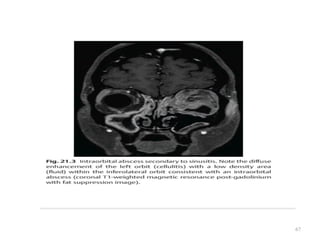

COMPLICATIONS

ORBITAL

Periorbital & Orbital

Cellulitis (Most often

secondary to Acute

bacterial Ethmoiditis)

- IV Antibiotic

- Surgical drainage of

ethmoidal sinus

ORBITAL COMPLICATIONS

• Most commonly following ethmoid sinusitis

• Lamina papyracea

• Osteitis or as thrombophlebitic process of

ethmoidal veins.